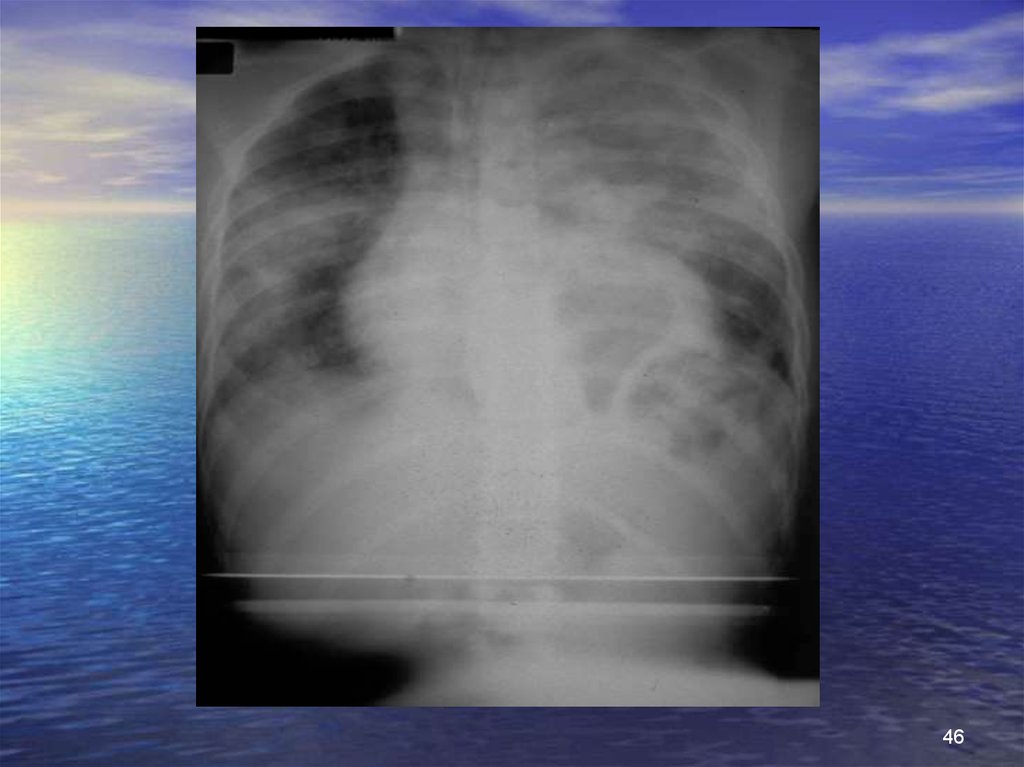

46.

46